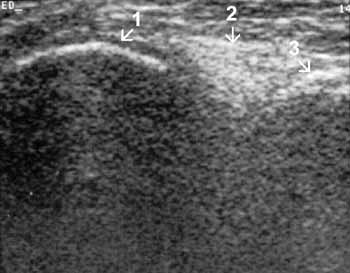

Рис. 11. Коленный сустав в норме. Задняя поверхность, сагиттальная проекция.

1 — медиальный мыщелок бедренной кости, 2 — задний рог медиального мениска,

3 — большеберцовая кость.